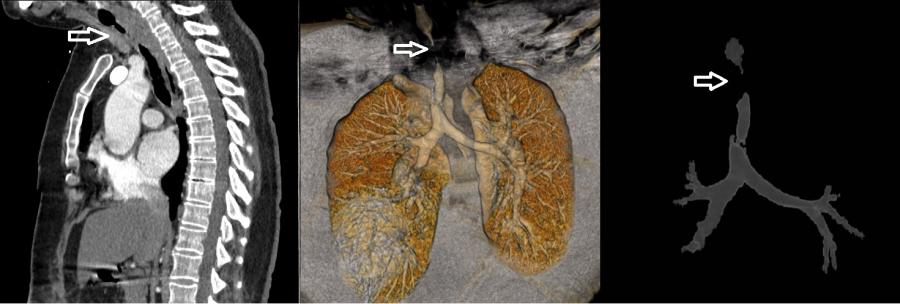

Geçirdiği COVID-19 enfeksiyonu nedeniyle yoğun bakımda mekanik ventilatörle tedavi görüp taburcu olan 52 yaşındaki kadın hastamız 1 ay sonra nefes darlığı şikâyeti ile göğüs cerrahisi polikliniğimize başvurdu. Yapılan detaylı tetkikler sonucunda hastamızın soluk borusunda 4.5 cm uzunluğunda daralma tespit edildi. Solunum sisteminin en önemli organlarından olan soluk borusunun hava yolunun açılması için acilen Rijit Bronkoskopi işlemiyle soluk borusundaki darlık genişletildi. Hastamızın solunumu geçici olarak rahatlatılıp sorunlu bölgenin detaylı teşhisi sağlandı. Yapılan değerlendirmeler sonucunda daralan soluk borusu kısmı için 2 hafta sonraya ameliyat planlandı. Başhekimimiz Prof. Dr. Celal TEKİNBAŞ liderliğindeki ekip tarafından yapılan ameliyatta hastamızın soluk borusundaki daralmış kısım kesilip çıkarıldıktan sonra sağlıklı uçlar birbirine dikildi. Ameliyat sonrasında sadece 5 gün hastanemizde yatan hastamız şifa ile taburcu edildi. Sonraki 10 günlük ve 2 aylık kontrollerinde de hastamızda hiçbir sorun bulunmamaktadır.

Pandemi döneminde mekanik ventilatör ile solunum desteği alan hasta sayısı artış göstermiştir. Bu tedaviyi alan hastaların yaklaşık % 5’inde soluk borusu darlığı gelişebilmektedir. Bu vakalarda kesin tedavi, darlık olan soluk borusu kısmının kesilip çıkarıldıktan sonra sağlıklı iki ucun birbirine dikilmesi yoluyla yapılan ameliyat iledir. KTÜ Farabi Hastanesi, bu vakaların tedavisini başarıyla yapan deneyimli bir merkezdir.